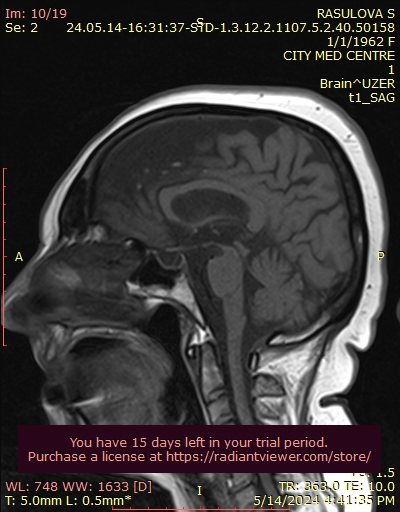

MRI of patient with PSP (The hummingbird sign)